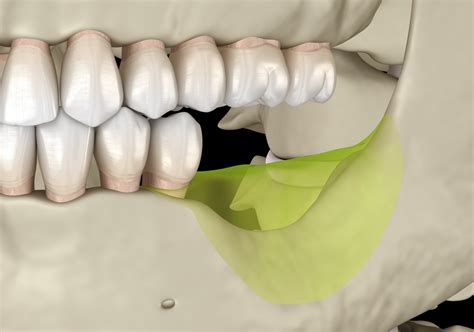

• Misalignment: The teeth may not align properly when the mouth is closed.

• Malunion or Nonunion: The bone may heal improperly, leading to misalignment or a nonunion, where the bone does not heal at all.

• Dental Issues: Problems with teeth alignment or function.